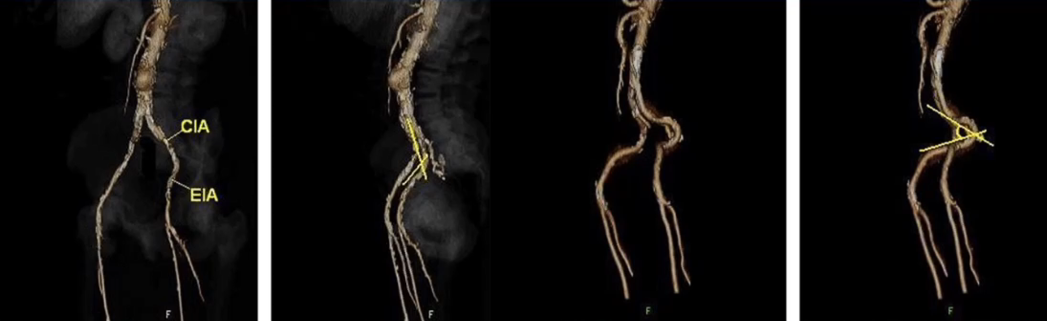

主髂动脉段的解剖特点

1. 迂曲、扭曲

走行特点:

向下(腹主)、向后外(髂总、髂内)、向前外(髂外),同时有Kinking和Tortuosity两种不同的迂曲方式。

从解剖学和文献中可以看到主髂动脉段各种迂曲和扭曲现象,因此,在选择治疗方法时需要特别注意,否则后期可能会出现问题,甚至在开通过程出现血管破裂情况。